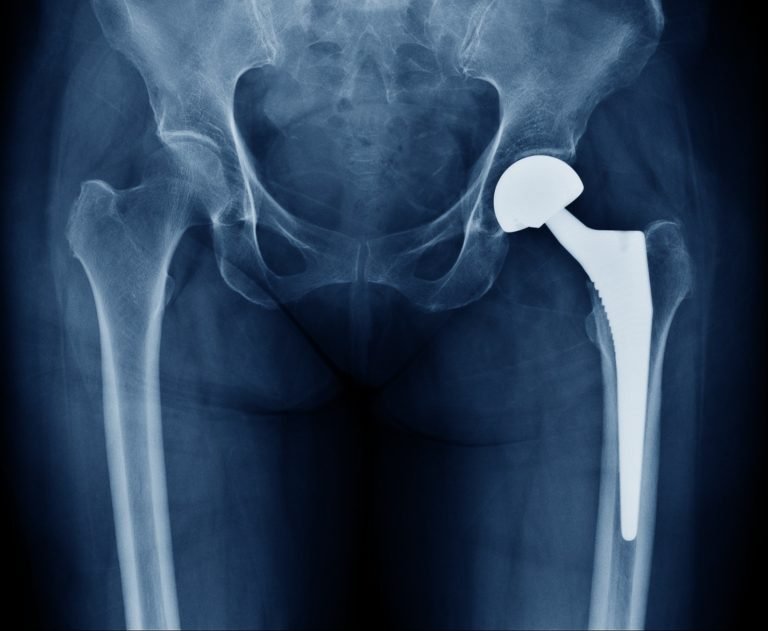

Failed Joint Replacement correction  In Jabalpur occurs when the implanted prosthetic joint no longer functions as expected or leads to ongoing pain, swelling, or stiffness after surgery. Moreover, this issue may develop weeks, months, or even years following the initial joint replacement. However, with advanced orthopedic care and modern surgical techniques available in Jabalpur, patients can effectively manage and correct failed joint replacements, thereby restoring mobility and improving overall joint function.

Diagnosis of Failed Joint Replacement

X-rays or MRI scans

When a joint replacement fails, revision surgery is often the most effective solution. During this procedure, the surgeon removes

the damaged implant and replaces it with a new one.Advanced facilities in Jabalpur use computer-assisted navigation and minimally

invasive techniques to ensure better alignment, reduced recovery time, and long-term relief.